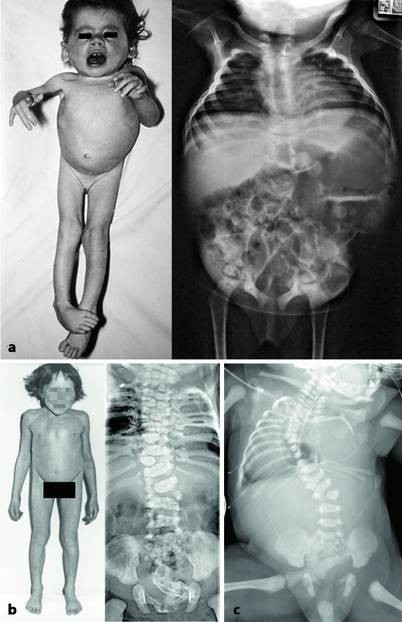

Die Symptome einer Hypoplasie bei Kindern variieren je nach betroffenem Organ oder Gewebe. Hier sind einige häufige Symptome, die auftreten können:

- Wachstumsstörungen: Kinder mit Hypoplasie können eine Verzögerung im Wachstum und in der Gewichtszunahme aufweisen. Sie können im Vergleich zu Gleichaltrigen kleiner und dünner sein.

- Körperliche Anomalien: Kinder mit Hypoplasie können körperliche Anomalien aufweisen, wie z.B. abnormale Gesichtszüge oder deformierte Gliedmaßen.

- Funktionseinschränkungen: Abhängig von der Schwere der Hypoplasie können Kinder auch Funktionseinschränkungen in Bezug auf Bewegung, Atmung oder Organfunktion haben.

- Bildgebende Verfahren: Bildgebende Verfahren wie Ultraschall, Röntgen oder MRT können verwendet werden, um das betroffene Organ oder Gewebe im Detail zu betrachten. Diese Verfahren ermöglichen es den Ärzten, die Größe, Struktur und Funktion des betroffenen Bereichs zu beurteilen und Anomalien festzustellen.